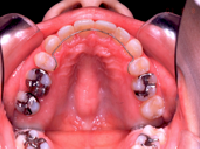

4) 治療に用いた装置 ストレートタイブマルチブラケットシステム(018x025スロット)

パラタルバー、前歯はセラミックブラケット

5) 抜歯 左右上顎第一小臼歯、下顎左右下顎第二小臼歯(計4本)

6) 治療期間 開始時から装置装着まで3か月、マルチブラケット期間2年3か月、保定期間4年

8) 考えられる治療効果 咀嚼能力および発音能率の向上、口唇が後退することで口元の審美性の改善